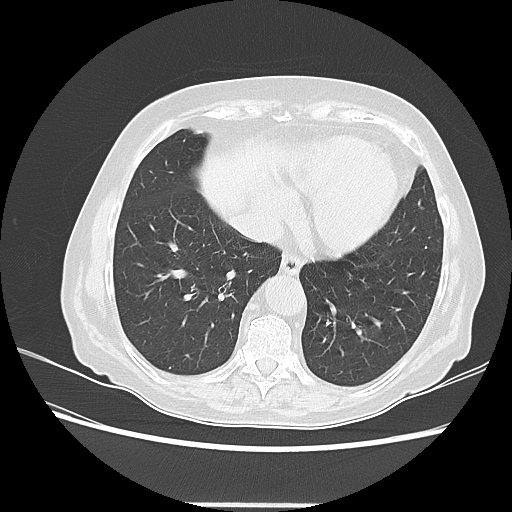

Generated VENOUS CT scan (A→B translation)

Lung window (WL -600, WW 1500 β†’ Low βˆ’1350, High +150)

Targeted Slice 70 - Lung Window Analysis (Generated vs Real Venous)

0.654

Lung SSIM

173.9

Lung RMSE

69.6

Lung MAE